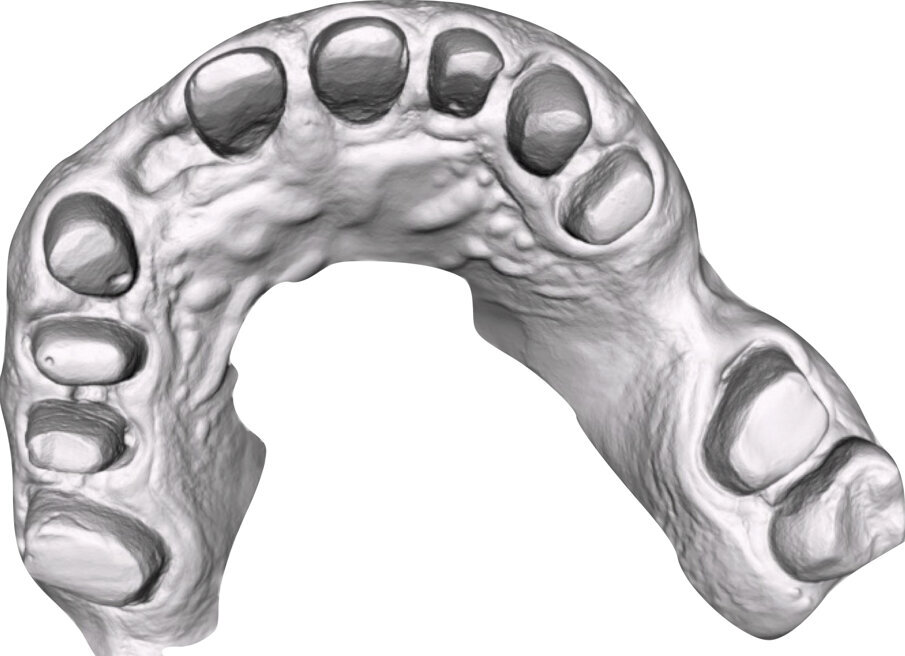

I modelli sono così importati in corretta posizione spaziale tramite il modulo exocad Virtual Articulator (Fig. 25). Non avendo a disposizione nel CAD l’analogo virtuale dell’articolatore Reference SL, viene impostato il sistema virtuale SAM, che usa lo stesso piano di riferimento axio-orbitale e geometria sovrapponibile al Reference SL. Per la programmazione virtuale dei parametri funzionali dell’articolatore si riesegue l’output dall’axiografia elettronica con Gamma Dental per SAM (Fig. 26). Si procede perciò ora con la modellazione CAD della ceratura mantenendo il riferimento dato dal piano occlusale individuato dai coni di centrica scansiti con l’articolatore (Fig. 27). L’articolatore virtuale consente una prima verifica dei rapporti occlusali tra gli elementi e un abbozzo di funzionalizzazione delle cuspidi con strumenti virtuali dinamici, che permette di arrivare ad un CAD design vicino alla morfologia ricercata (Figg. 28-33). Il modellato è ora fresato in cera Yeti Dental al CAM con fresatore VHF Cam5-S1 ed i denti in cera, tutti singolarmente sfilabili, sono posizionati sui modelli eseguiti con stampa 3D.

Il fresato ottenuto è poi riportato su articolatore Reference SL – già opportunamente programmato – e viene dall’Odontotecnico competente più precisamente funzionalizzato secondo i criteri della programmazione funzionale sequenziale, evidenziando con cere colorate i rapporti di centrica, le funzioni di mediotrusiva e protrusiva e le protezioni retrusive. I monconi sfilabili consentono la modellazione della sequenzialità mediotrusiva con la guida incisale indicata dalla registrazione axiografica (blu) (Figg. 34-37). La ceratura sequenziale è ora scansita con Sirona InEos X5 su Exocad, ed il modellato viene ricontrollato al CAD per spessori, connessioni e morfologia, e nella regolazione degli offsets per la ripreparazione dei monconi, ed è inviato al CAM per la fresatura dei II provvisori in Bredent breCAM.multicom, un PMMA con microriempitivo ceramico ad alta stabilità, su Dental Plus 5 Axis Milling Machine. La rifinitura dei monconi è seguita da ribasatura dei II provvisori in TRP - previo isolamento di tutte le superfici funzionali - e gli stessi sono poi rifiniti e lucidati. I soli elementi 3.3, 4.2 e 4.3 sono rimodellati in regione incisale con addictions in composito, secondo la morfologia studiata in ceratura. La consegna conferma la buona integrazione dei manufatti dal punto di vista estetico, occlusale, articolare e neuromuscolare, con controllo occlusale conforme al progetto (Figg. 38-42).

Il paziente utilizza questi secondi provvisori per otto settimane, durante le quali conferma la buona integrazione dei restauri e la soddisfacente funzione occlusale. Ciò è verificato con l’esecuzione di una nuova axiografia elettronica che già a due settimane dalla consegna evidenzia una buona risposta muscolare al nuovo design occlusale ed alla nuova postura mandibolare in TRP (Figg. 43-46). Provvediamo infine alle impronte per la costruzione dei manufatti definitivi in Zirconia-ceramica. I modelli sono scansiti in laboratorio con inEos X5 (Dentsply Sirona) su exocad (Figg. 47-49), ed una seconda scansione viene eseguita con i provvisori del Paziente posizionati sui modelli (Figg. 50-52). Il CAD consente di eseguire un matching fra le due scansioni, per cui i secondi provvisori utilizzati in TRP, con funzione occlusale sequenziale già completamente programmata, sono utilizzati per definire le morfologie dentali definitive di tutti gli elementi da restaurare (Figg. 53, 54) secondo il rapporto intermascellare definito (Figg. 55-58). Si esegue quindi fresatura al CAM della protesi definitiva in zirconia (Figg. 59, 60), la stratificazione e finitura ed infine la consegna al Paziente con cementazione in Panavia V5 (Figg. 61-65).